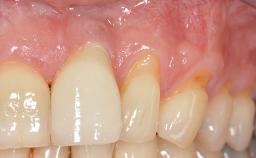

A 30-year-old woman was referred by her general dentist for evaluation of an esthetic complication related to previous implant treatment for congenitally missing maxillary lateral incisors. The patient’s chief complaint was the inadequate esthetic appearance of her smile. The case demonstrates the use of a combined approach to achieve optimal results. Two different flap designs - a tunnel technique and a coronally advanced flap - are employed based on the surgical objectives for the affected site.

Soft Tissue Anatomy Intact Defective